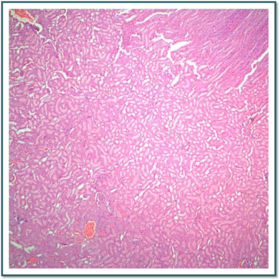

Láminas de Histología

Description

Laboratorio de histología, Bibliografía Ross Pawlina 5ta Edición.